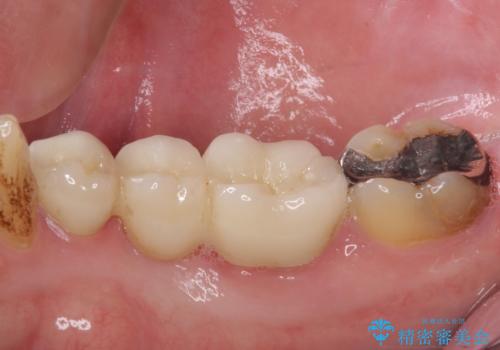

- 近医でむし歯治療をしたものの、術後も痛みが続くとのことで来院された患者様です。

当初は根管治療を再度行うことで痛みが引くことを期待しましたが、該当歯の歯周ポケットが局所的に深くなっていることから、歯に穴が開けられているか破折している可能性が疑われました。

歯肉を開いたところ、周辺の歯槽骨は全て炎症で失われ、破折と同等の穴が開けられていることが分かったため、抜歯を行いフルジルコニアブリッジにて補綴することとしました。